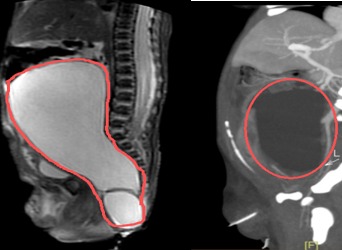

800克肿瘤“霸占”新生儿腹腔,多学科联手打赢生命第一战

在妈妈肚子里,萌萌(化名)就被发现骶尾部长了一个“大瘤子”——巨大的骶尾部畸胎瘤。这个肿瘤在她出生时已达800克,占据了大半个腹腔,挤压肠管,紧贴盆腔周围器官,生命伊始就面临严峻挑战。珠江医院多学科团队携手护航,通过高难度单孔腹腔镜微创手术,成功拆除了这颗“定时炸弹”,创造了生命的奇迹。产检惊现胎儿“腹中巨瘤”萌萌妈妈在孕34周的产检中,发现肚子里的宝宝屁股上…